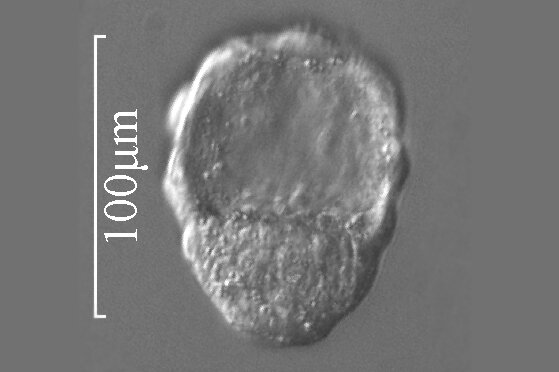

Bruzdkowanie jest pierwszym etapem życia zarodkowego. Rozpoczyna się pierwszym podziałem zygoty, około 30 do 36 godzin po zapłodnieniu. Komórki powstałe po podziale zygoty nazywane są blastomerami. Zarodek zbudowany z 12‑16 blastomerów ma formę grudki i nazywany jest moruląmorulą. W dalszym etapie blastomery rozsuwają się, a zarodek przyjmuje formę pęcherzyka, z jamą w środku. Jest to blastocysta, która przesuwa się przez jajowód i dociera do macicy, gdzie ok. 6. lub 7. dnia od zapłodnienia następuje implantacja zarodka w błonie śluzowej macicy.

6 dzień | 0,15–0,2 mm | Powstaje blastocysta, która następnie ulegnie implantacji w ścianie macicy. ![]() Źródło: Englishsquare.pl Sp. z o. o., licencja: CC BY-SA 3.0. | |